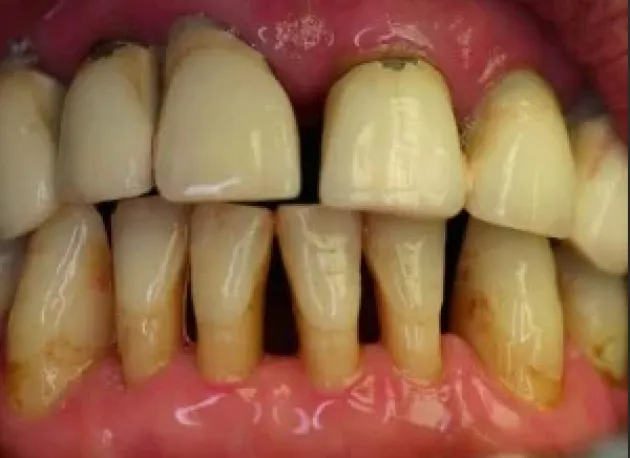

Această procedură implică inserarea unui număr de implanturi dentare (4, 6 sau 8) în cavitatea bucală. Numărul exact de implanturi este determinat de către medicul chirurg, în funcție de evaluarea clinică, de structura osoasă și de cerințele individuale ale pacienților.